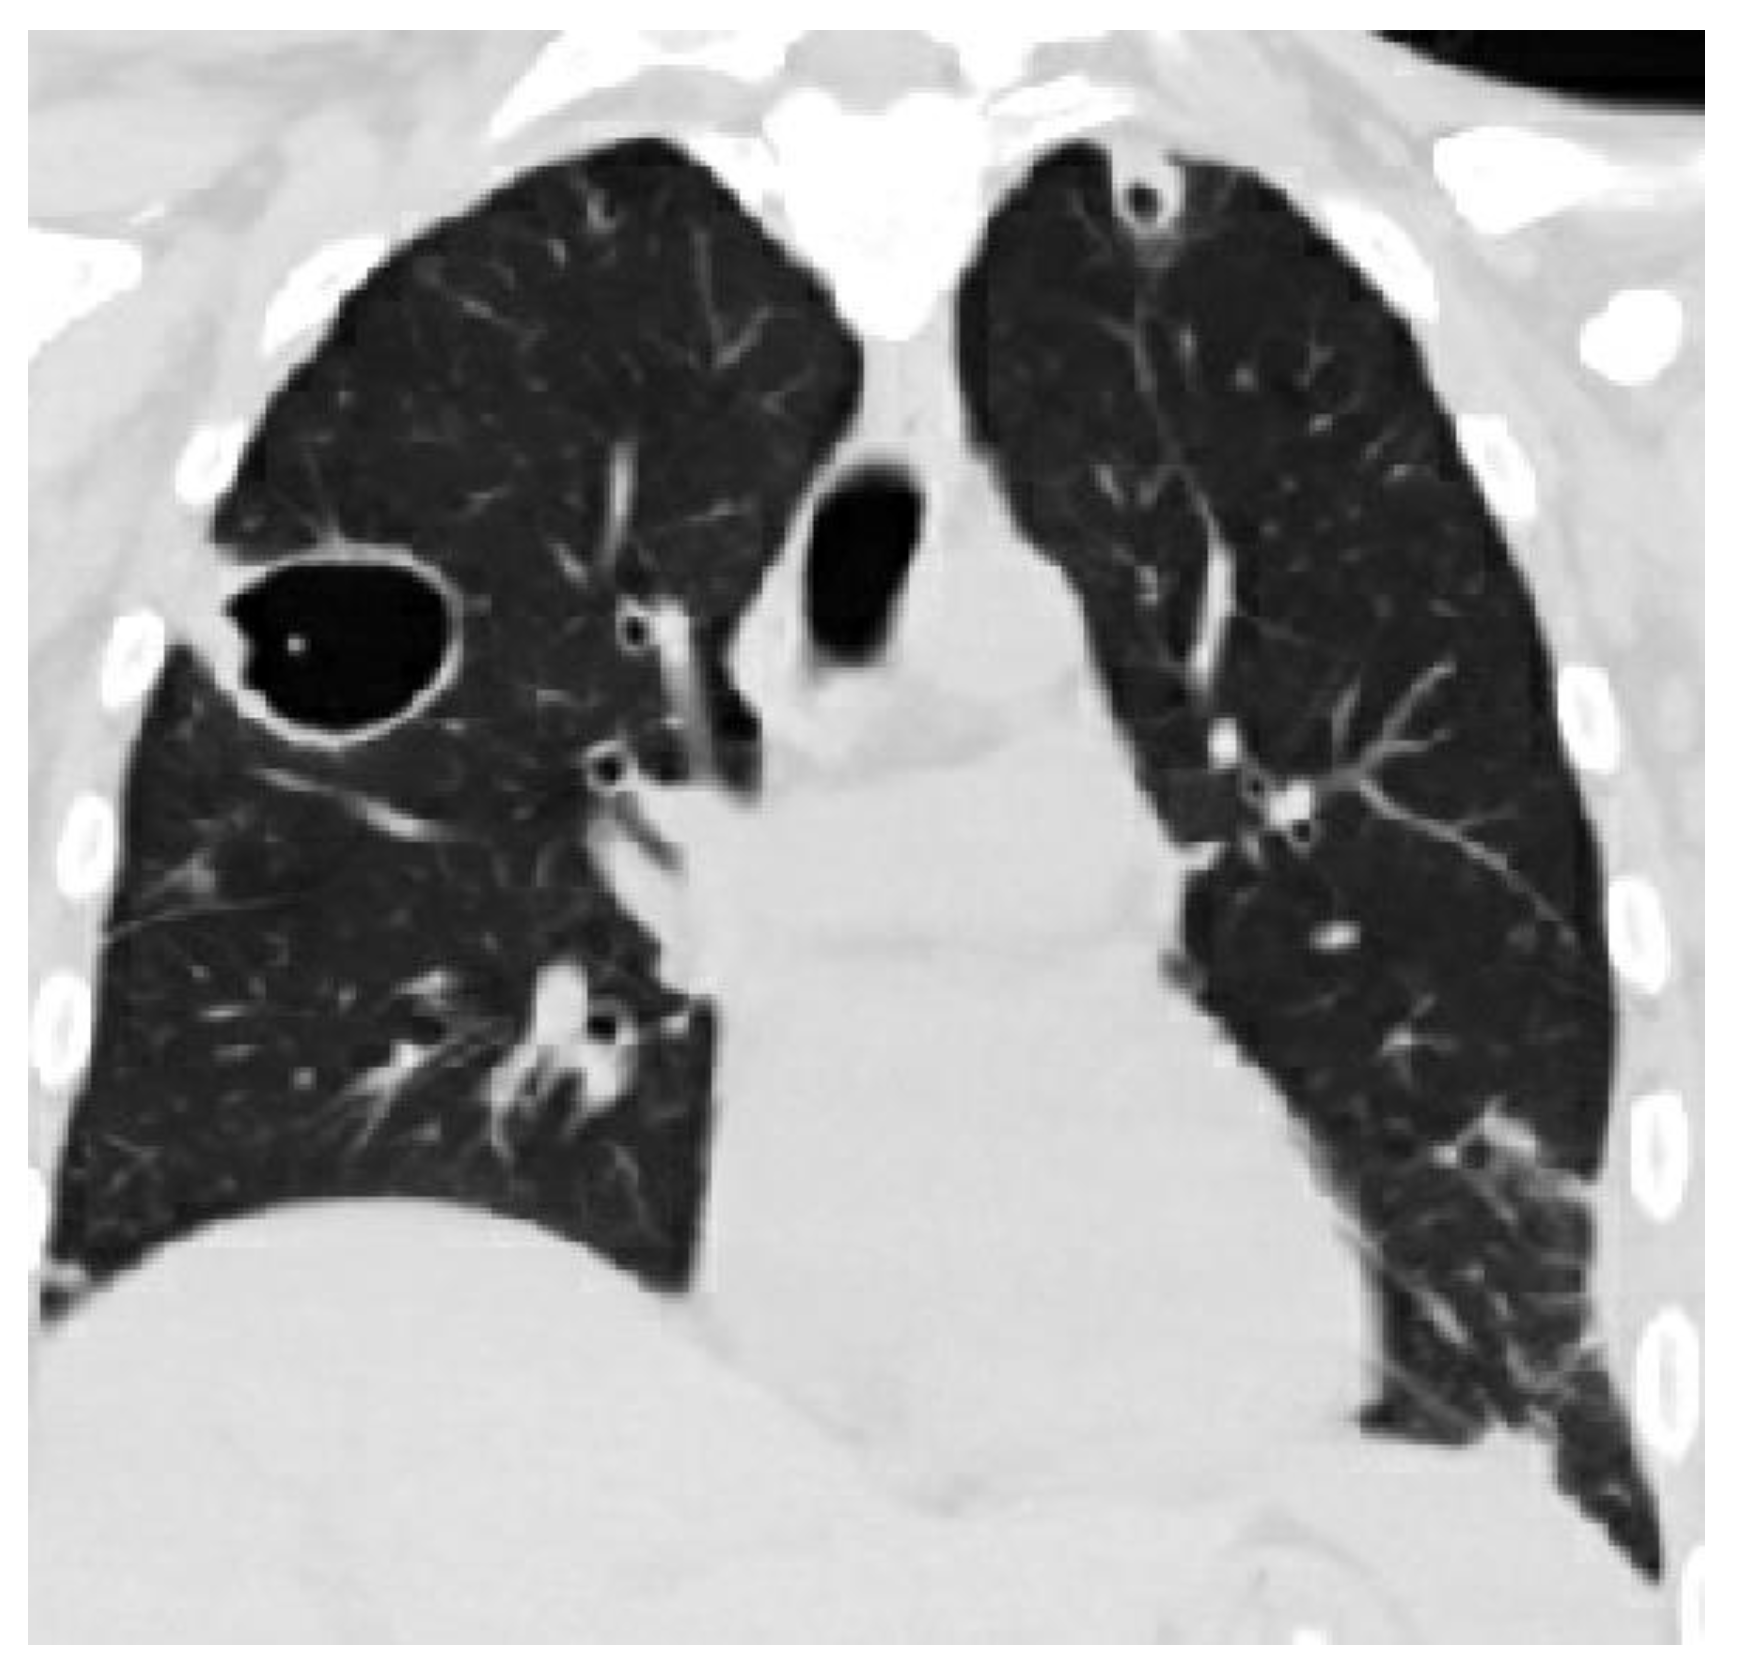

In patients with septic pulmonary emboli, the chest CT reveals bilateral pulmonary abnormalities in over 80% of the cases. The most common lesions are nodular opacities. Necrosis (cavitation) is seen in slightly over 50% of these patients. Other characteristic but less common lesions include wedge-shaped opacities and the feeding vessel sign (see Figure 3) [7].

Figure 3.

A CT scan of a patient with radiographic evidence of septic emboli.